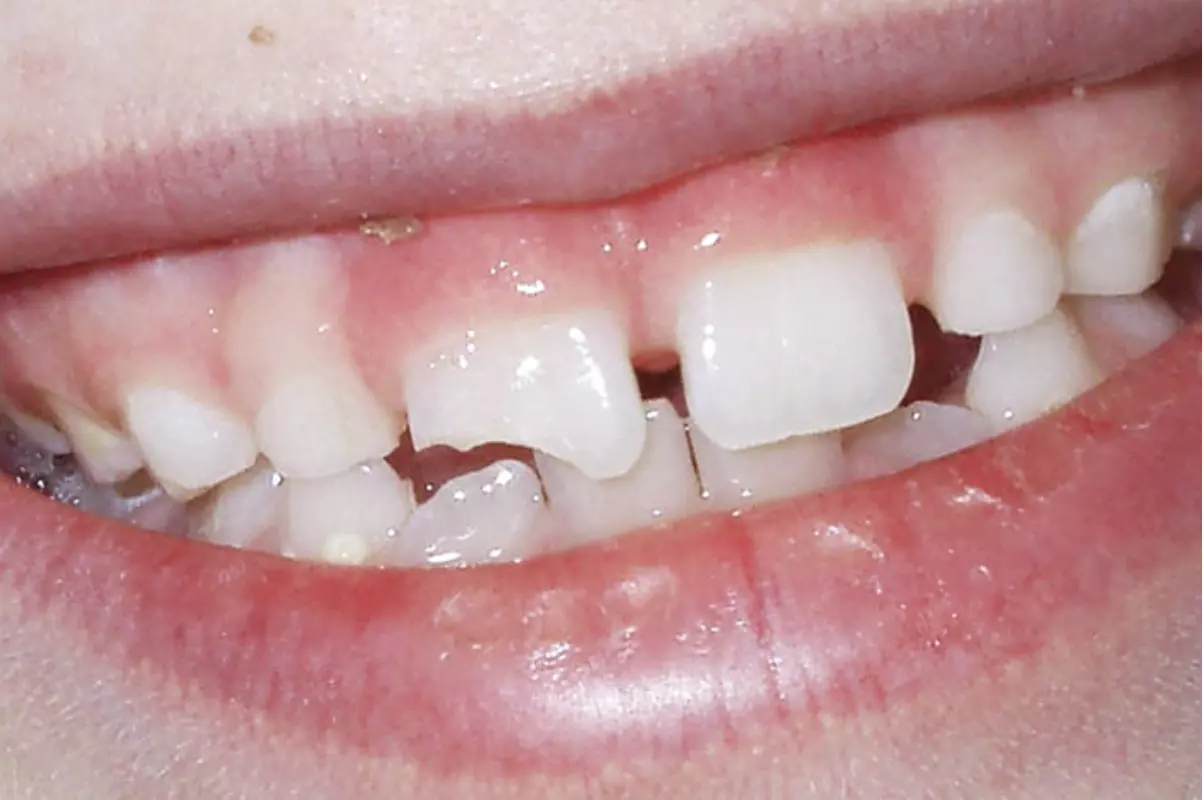

Травмы молочных зубов у детей – не редкость, в особенности у малышей в возрасте 1-3 лет. Своевременное обращение к детскому стоматологу в NikaDent и правильные действия в первые минуты после получения травмы позволяют сохранить зуб ребенка, дождаться его физиологической смены впоследствии.